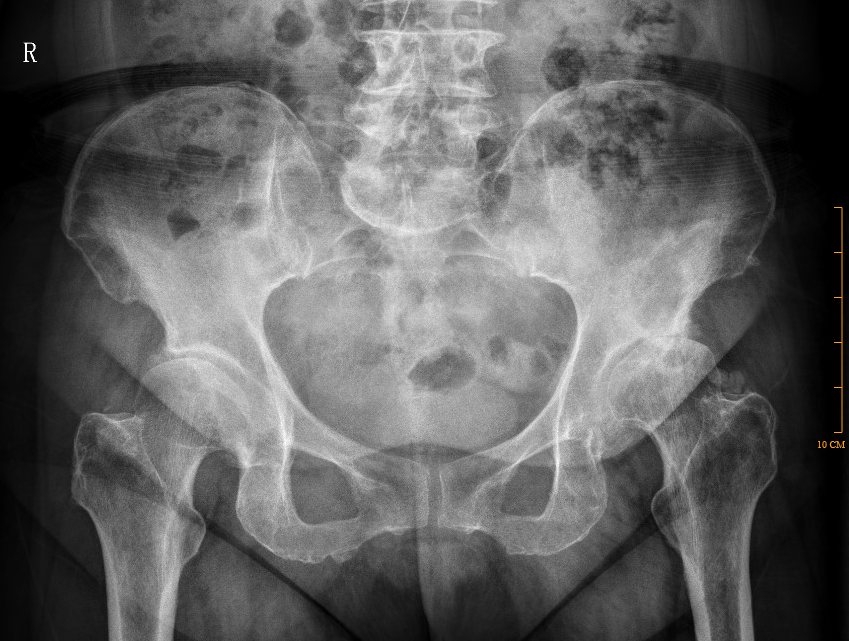

【影像】骨盆平片阅片见左侧髋关节内侧间隙变宽、上方间隙变窄,股骨头外形欠圆滑,内见椭圆形低密度区。

左侧环跳穴压痛(+),腹股沟中点压痛(+),“4”字试验(+),痛点位于腹股沟中点,髋关节屈伸受限。骨盆平片阅片见左侧髋关节内侧间隙变宽、上方间隙变窄,股骨头外形欠圆滑,内见椭圆形低密度区。故高度怀疑“股骨头坏死”。 MR报左侧股骨头改变,考虑股骨头缺血性坏死,确认“股骨头缺血性坏死”临床诊断。